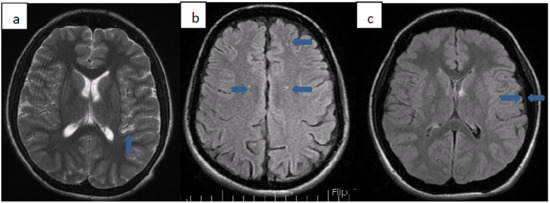

We detected various pathologies on cranial MRI images of 10 (33.3%) patients. Patients with pathology on MRI are summarized in Table 3. Three of these patients (33.3%) were Syrian citizens. The average age of diagnosis of patients with pathology on MRI was 25 months. All but one of the patients received transfusion therapy from the time of diagnosis. Transfusion treatment was started 29 months after diagnosis, only for patient number 9. The total chelation time of the patients except 3 was determined. Accordingly, the average duration of chelation therapy these patients received was 9.7 years. In 3 of these patients, millimeter-sized ischemia-compatible lesions were found in the cerebral white matter, which did not fit any arterial area. Five patients had hyperintense lesions in the basal ganglia (2 globus pallidus, three putamens). One of our patients had thickening of the dura mater, and one of our patients had cerebral atrophy. Cardiac involvement was not found in any of these patients. While only patient 4 had insulin resistance, the other patients did not have any endocrinopathy. No significant difference was found between gender or nationality and MRI pathologies (Figure 1).

In our study, we found various pathologies on the cranial imaging of 1/3 of our patients. Five of these had hyperintense lesions secondary to iron accumulation in the basal ganglia. Three of the remaining patients had millimetric ischemic foci due to hypoxia, 1 had dura mater thickening due to extramedullary hematopoiesis, and 1 had cerebral atrophy. The most common pathology we encountered in cranial MRIs was lesions in the basal ganglia. Three of our patients had lesions in the putamen and 2 in the globus pallidus. Metafratzi et al. showed that more iron accumulates in the putamen caudate nucleus and cortex in patients with thalassemia major than in healthy people. In various studies performed later, it was shown that iron accumulation is also present in the thalamus, red nucleus, and choroid plexus [9,10,11,12]. The second most common cranial MRI pathology was millimetric ischemic changes. We found ischemic foci in the cerebral white matter in 3 of our patients. In recent studies, thromboembolic events were reported with a rate of 0.9–29% in thalassemia patients [13,14,15,16,17,18,19]. These ischemic foci that we saw in our patients were minimal areas due to microemboli. Dural thickening due to extramedullary hematopoiesis is extremely rare. Studies of dural thickening resulting from intracranial extramedullary hematopoiesis in children with thalassemia are generally at the level of case reports [18,19]. In our study, we detected dural thickening in 1 patient. While extramedullary hematopoiesis is more common in other parts of the body, it is rare intracranially.

Figure 1. (ac): Axial T2 (a) and Axial FLAIR (b) weighted images show multiple foci of hyperintensity that are related to asymptomatic brain ischemia. Axial FLAIR (c) image show widened epidural tissue.